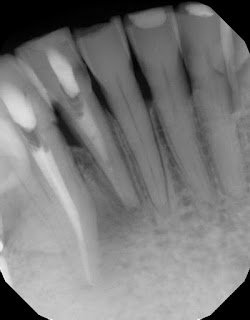

There was concern of a possible root fracture, but none could be see internally with microscope. CaOH medicated dressing was placed after initial debridement and NaOCl irrigation.

After 3 months in CaOH, we opened and examined again and could find no fractures. Another application of CaOH medicated dressing was placed.